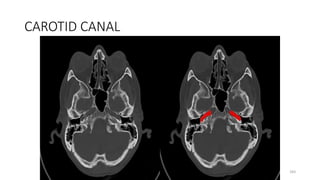

Carotid canal